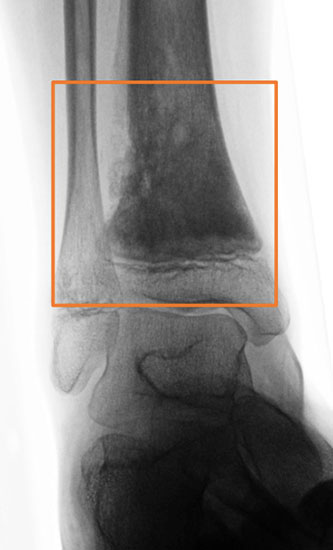

In unserem eigenen Patientengut werden alle gut- und bösartige Knochen- und Weichteil­tumoren des Fußes, einschließlich dem Bereich der distalen Metaphyse der Tibia und Fibula als Fußtumoren definiert. Die Metaphyse ist hierbei durch ein gleichseitiges Rechteck (Qua­drat) festgelegt (Abb. 5), das seine Basis am breitesten Teil der Wachstumsfuge hat (Ruedi, 2000). Explizit ausgeschlossen hiervon werden alle oben genannten Pseudotumoren.